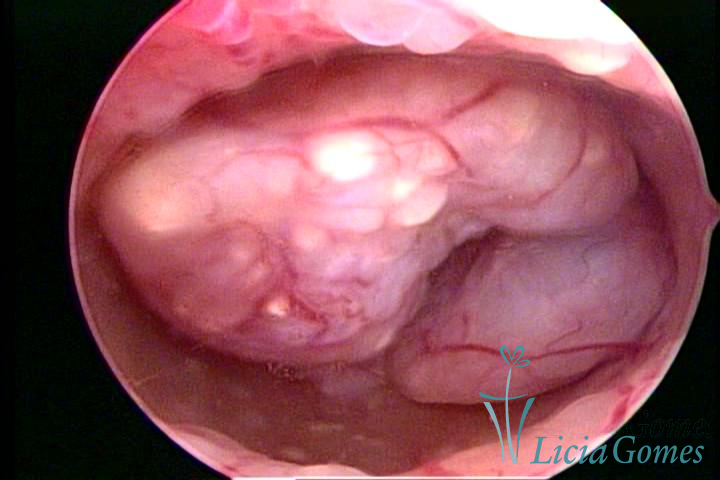

Salientando que cabe à microscopia (Histopatológico), o diagnóstico diferencial da Hiperplasia com atípias e o Adenocarcinoma de endométrio ou outro tipo de neoplasia endometrial.

Este pode apresentar uma gama variável de aspectos macroscópicos, com aspecto pseudopolipoide; lembrando tecido cerebroide ou com reação deciduoide;a vascularização superficial é mais evidente e com vasos em formatos de saca-rolha ou espirais visualizando também a vascularização com atípias, com aumento do calibre dos vasos superficiais, pode ser encontrado também tecido em necrose, poderá haver um pequenos dendritos (papilomatoso).